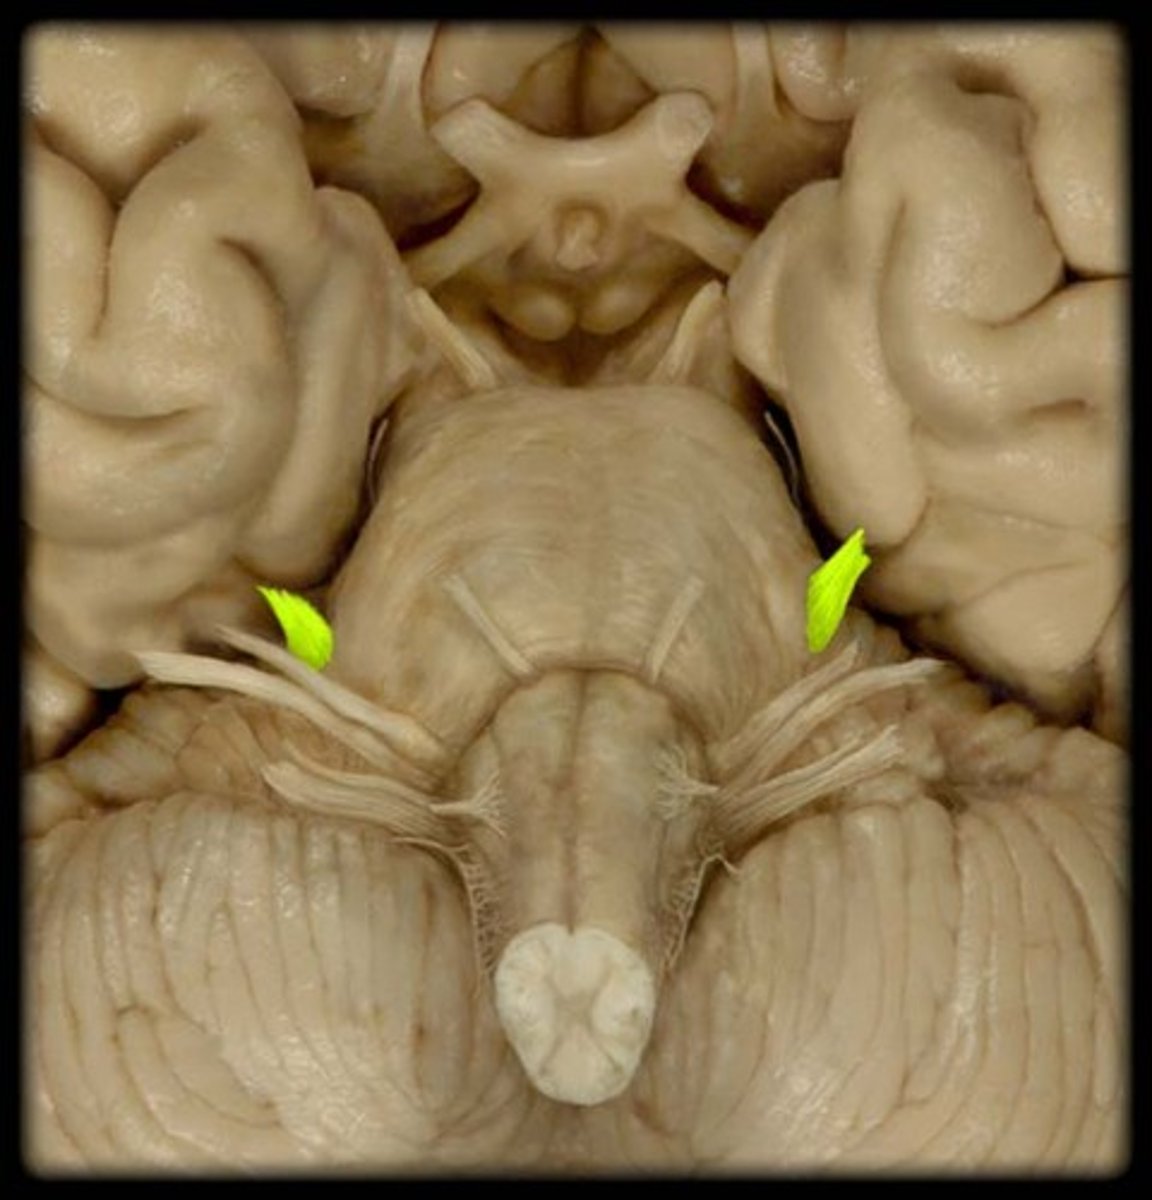

inferior colliculi

the two inferior bumps of the tectum. Responsible for auditory reflexes